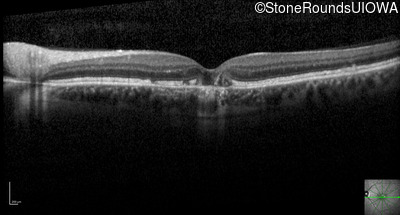

Optical Coherence Tomography - Right - 20/20

Exemplar / OCT Stack